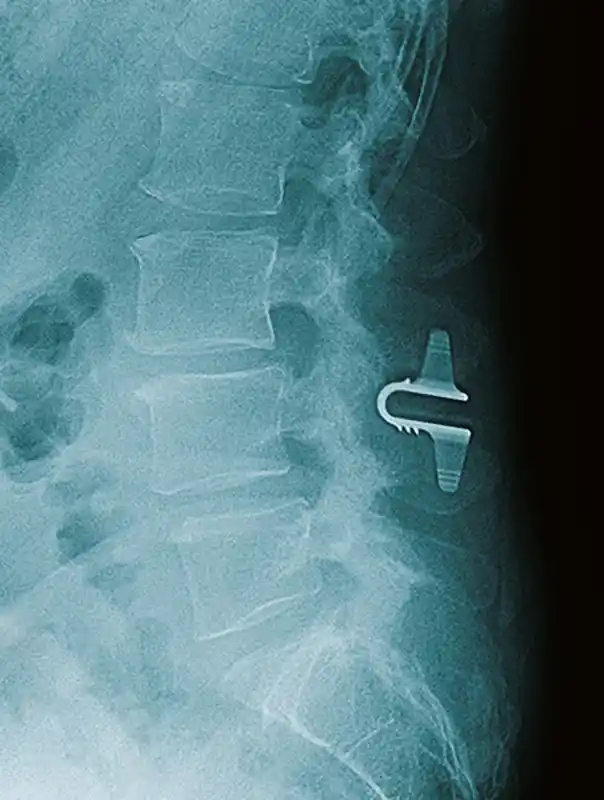

The Coflex® Interlaminar Stabilization® Technology is an interlaminar functionally dynamic implant designed to impart a stabilization effect at the operative level(s) after a decompression surgery while retaining natural motion. It consists of a single, U-shaped component, fabricated from medical grade titanium alloy (Ti6Al4V, per ASTM F136 and ISO 5832-3). In clinical use, the “U” is positioned horizontally, with its apex oriented anteriorly and the two long arms of the “U” paralleling the long axis of the spinal processes. The implant bears load on interlaminar bone, and compresses upon spinal extension. The bone-facing surfaces are ridged to provide resistance to migration.

Coflex X-Ray

The Coflex device is an alternative to fusion for a subset of lumbar spinal stenosis patients.